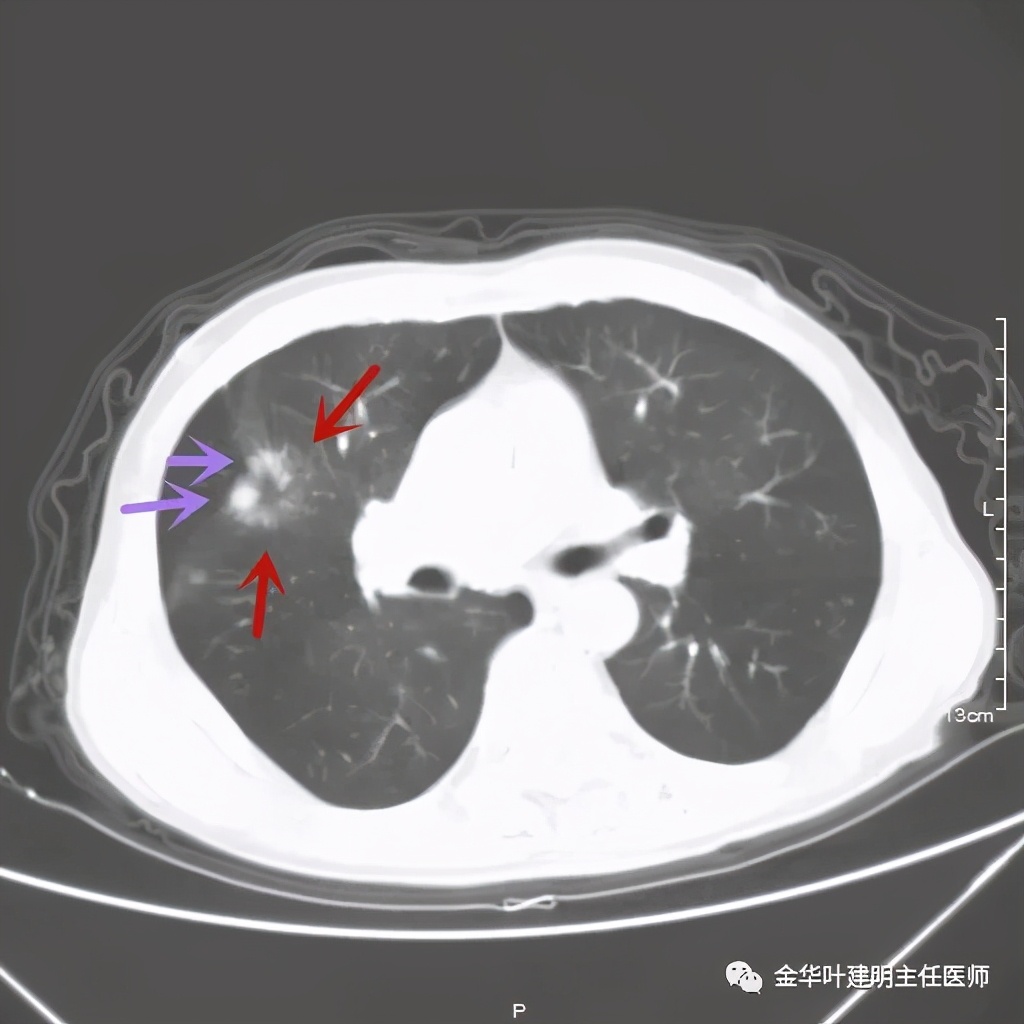

上图是穿刺时的某个层面,病灶的细毛刺征比较明显(蓝色箭头),病灶的边缘是不平的,而且有细短的毛刺样突向周围肺组织,这可是恶性的特征

桔色箭头示病灶周围血管征明显,有较粗的血管进入病灶,较细的也有

上图紫色箭头示明显的叶间胸膜牵拉,红色箭头示病灶,中间还有空腔,边缘有细毛刺,感觉上病灶就是有收缩力而僵硬的

上图也见细毛刺,但不是特别广的范围,有的边缘还是相对比较光滑了点